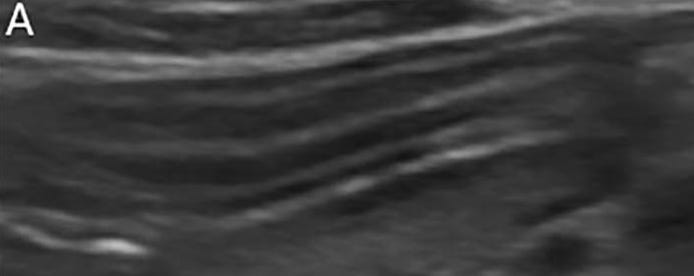

Imagen ecográfica normal de la pared intestinal: